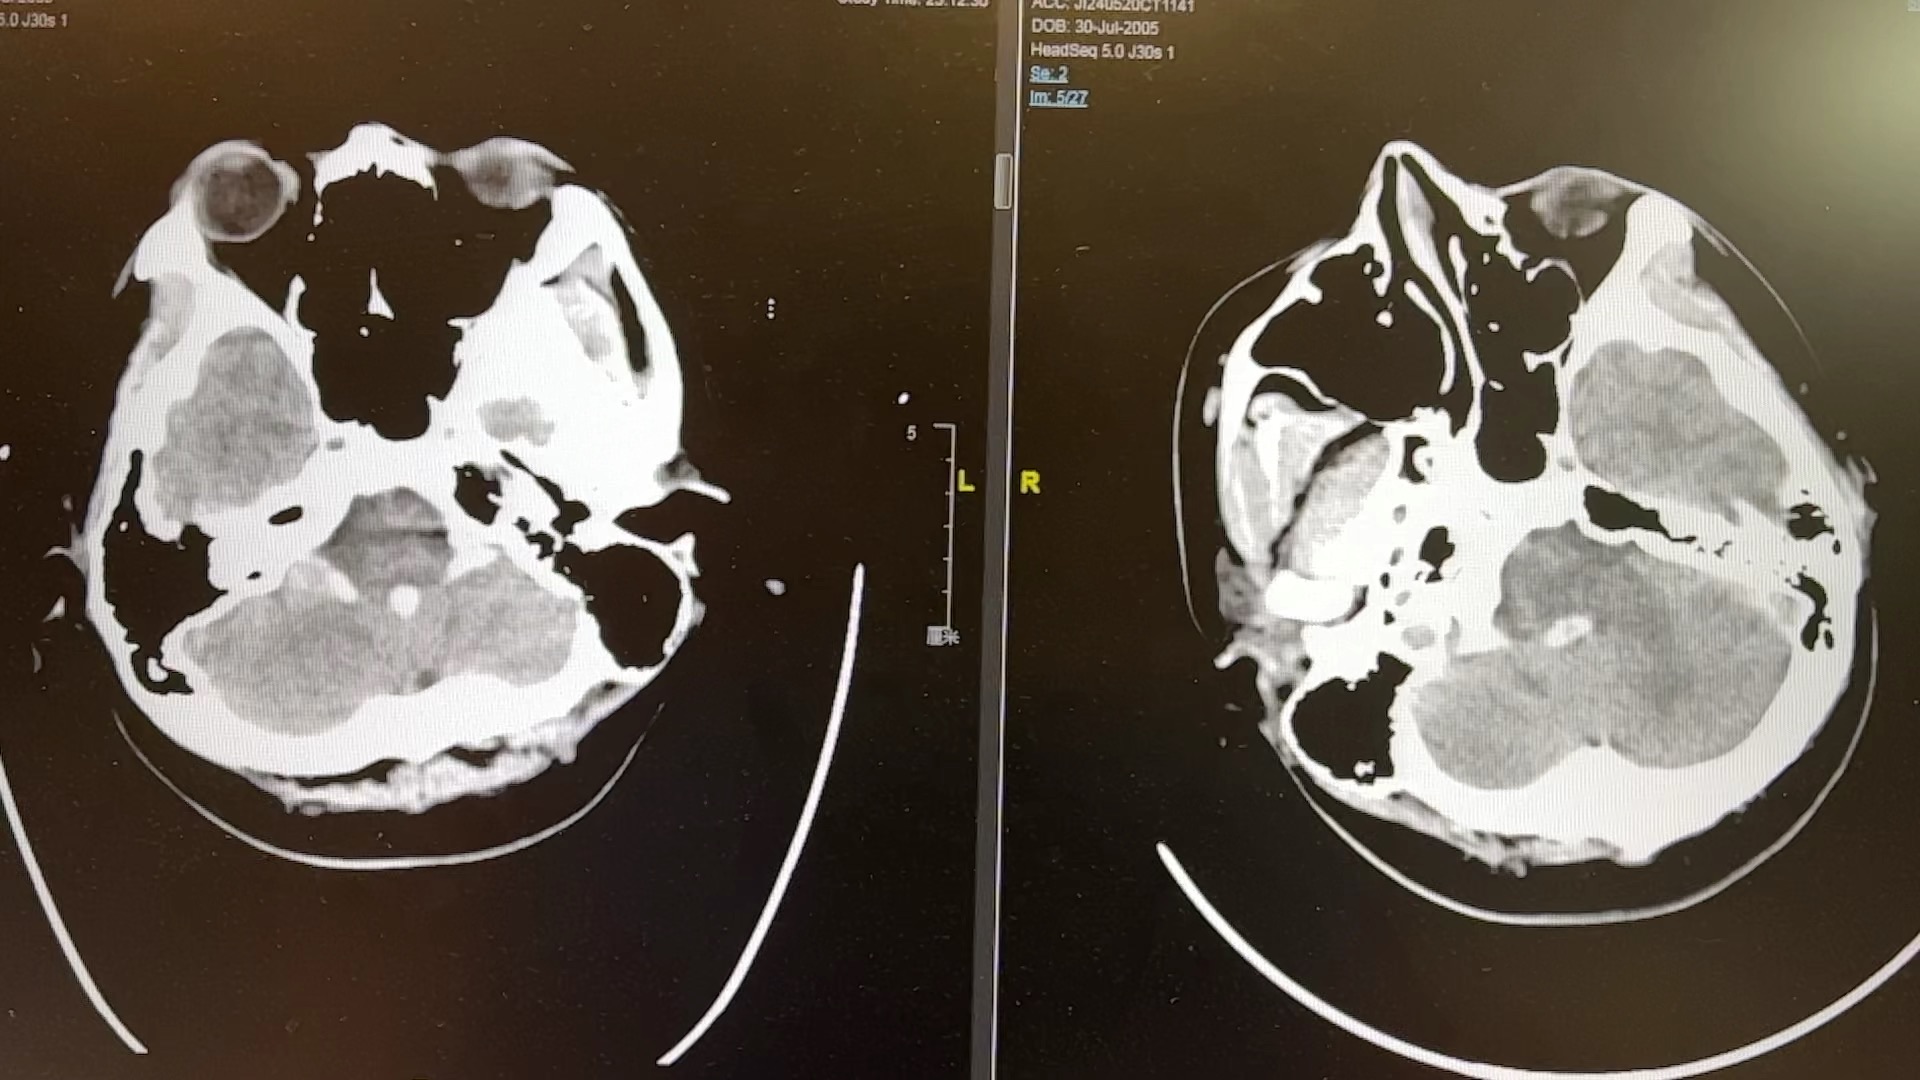

患者18岁,上课突发视物模糊,后出现呕吐🤮,意识障碍… …

主要诊断:左侧枕叶出血破入脑室🩸,蛛网膜下腔出血

术前术后对比

上方是术前照片

下方是术后照片

补充:患者术后第四天顺利拔除气管插管,自主呼吸可,对答切题